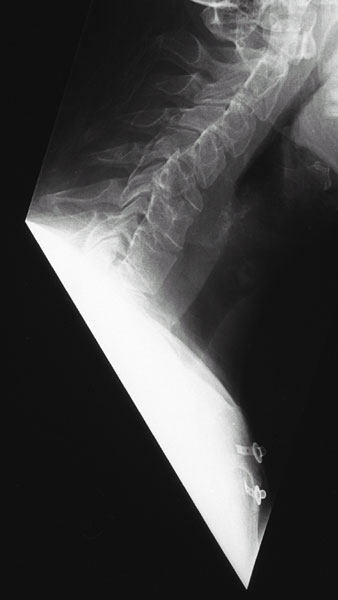

Abb. 1+2 von links

Instabiler Bruch des 5. Halswirbel-Körpers mit Abknickung der Hals-Wirbelsäule und Bruchspalt im Wirbelkörperhinterkantenbereich.

(links normale seitliche Röntgenaufnahme, rechts Schichtbild in der Computertomographie